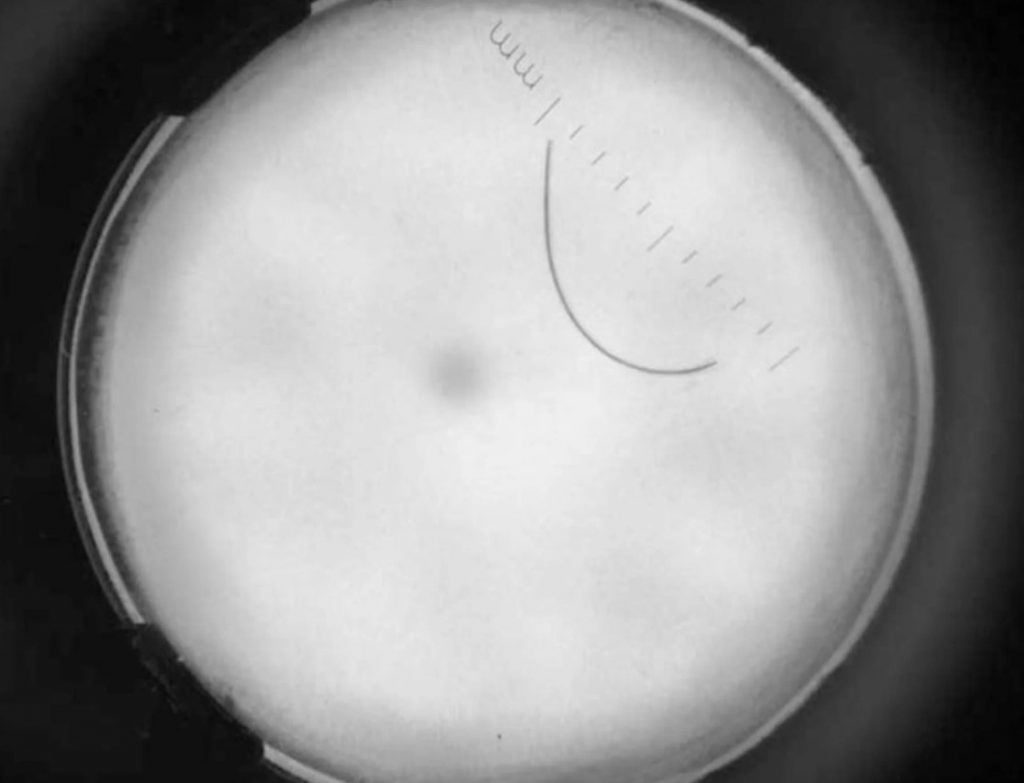

SãoPaulo Üniversitesi’ndeki araştırmacılara göre topuğa daha yakından bakıldığında topuğa yapışmış gibi görünen tek bir saç teli fark edilmiştir. Gerçekten de, büyüteçle yapılan ayrıntılı bir muayenede, erkeğin topuk derisine nūfuz etmiş küçük bir kıl gözlemlendi.

10 Milimetre Uzunluğunda Saç Kιymιğı

Doktorlar cımbız kullanarak 10 milimetre uzunluğundaki bu kılı yerinden çιkardılar. Adama kütanöz pili migrans (cutaneous pili migrans-CPM) teşhisi konuldu; bu, bir kıl gövdesi veya kıl p∂rç∂sının cilt yüzeyine y∂pıştıktan sonra zamanla gömülü hale geldiği nadir gerçekleşen bir durumdur.

Yayımlanan bu yeni raporun araştırmacıları; kılların cilde girdiğinde, hastanın ayağının hareketlerinden dolayı “sürünen bir düzende” göç edebildiğini söylemiştir. İlginç bir şekilde, bu sürünen şekil, kancalı kurtların neden olduğu bir cilt hastalığı olan kütanöz larva migrans hastalığına sahip insanlarda görülen yılan benzeri dōkūntüye benzeyebilir.

Ancak, kırmızı ve k∂barık görünen kancalı kurt dōkūntülerinin aksine, bunda saç kılları derinin altında siyah, iplik benzeri bir çizgi şeklinde görünür.